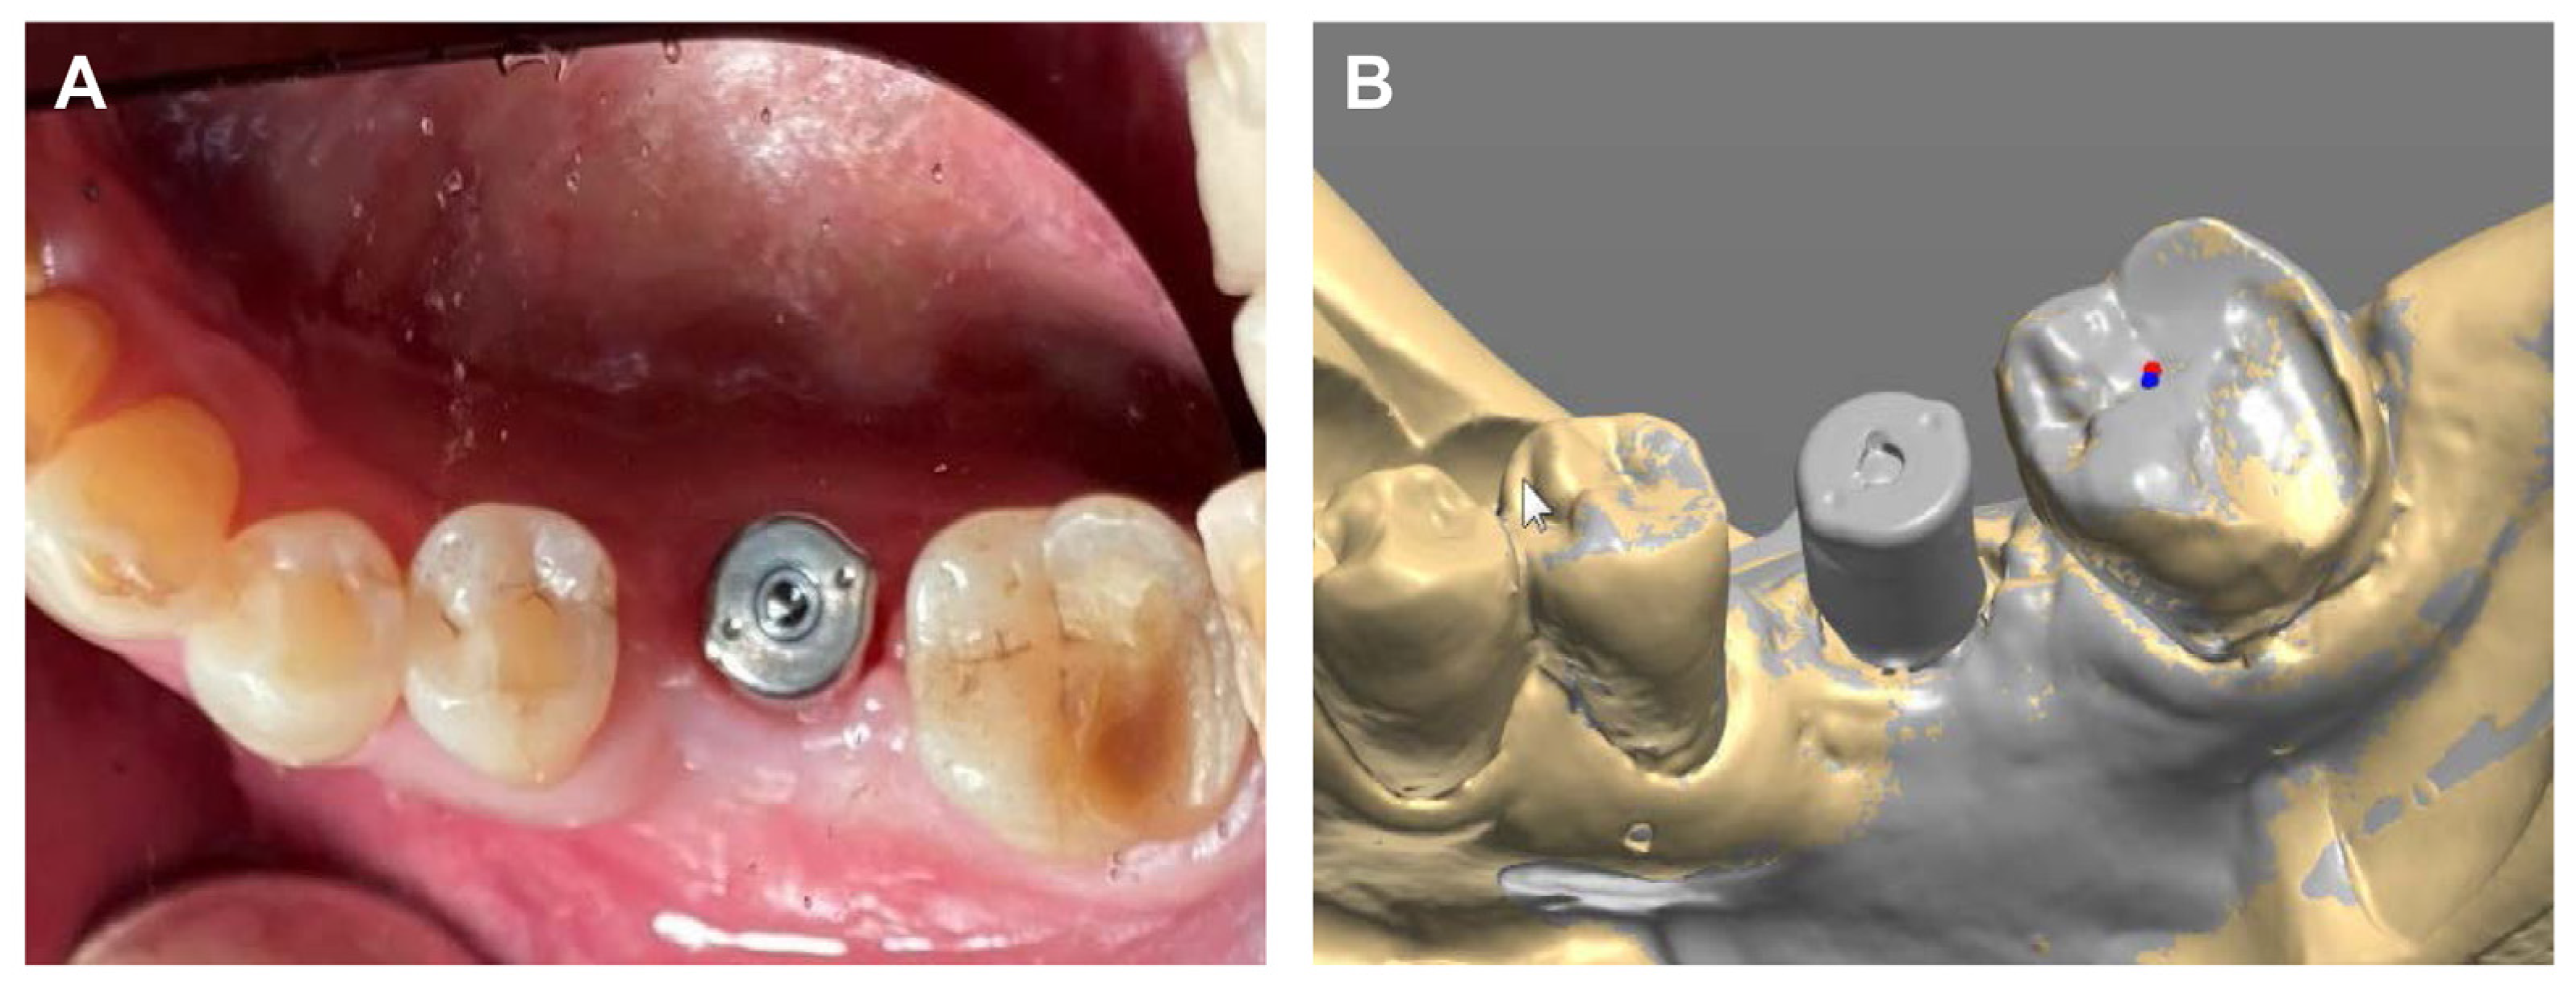

The final prosthesis was connected to the multi-abutment through the abutment screw in the oral cavity of the patient. After the intraoral adjustment, the prosthesis was connected to the implant through using an abutment screw with a torque of 25 N/cm2. The screw access hole was sealed using Teflon tape and composite resin (Gradia Direct A3, GC, Tokyo, Japan) to complete the procedure (Figure 6A), and the accuracy of the connection of the implant prosthesis was confirmed through a periapical radiograph (Figure 6B).

Figure 6. Final delivery of implant prosthesis. (A) Intraoral photograph, (B) Periapical radiograph.